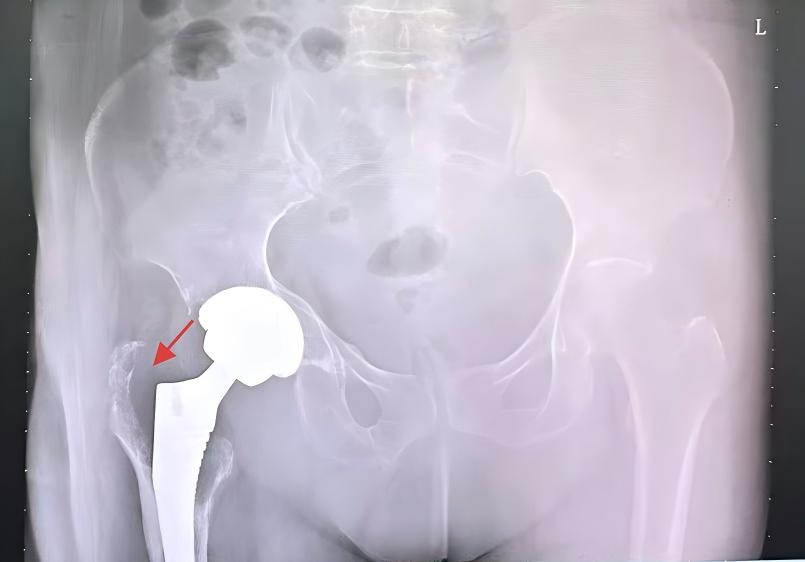

在骨科手术室里,全髋关节置换术(Total Hip Arthroplasty, THA)是一项极具代表性的手术。它通过植入人工关节,帮助无数股骨头坏死、髋关节骨性关节炎或股骨颈骨折的患者重获行走能力,摆脱疼痛。然而,手术过程中有一个看似不起眼的环节:医生会将病变的股骨头截下,以便安装人工假体。

翻修手术中的“地基”重建

随着人工关节置换术的普及,关节翻修手术的数量也在逐年上升。在髋关节或膝关节翻修术中,医生常面临严重的骨量丢失(骨溶解)。

股骨头经过特殊的加工(如制成骨颗粒或骨条),可以通过打压植骨技术(Impaction Bone Grafting)填充在髋臼或股骨侧的骨缺损处。